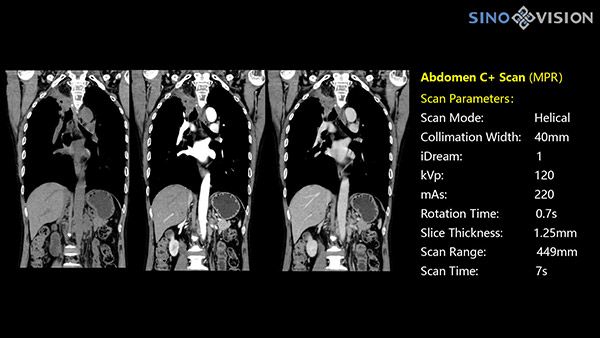

Инновационный 128-срезовый компьютерный томограф SinoVision InsitumCT 568 – это сочетание высокой скорости работы, низкой дозы и максимума возможностей для подавляющего большинства клинических случаев, как в рутинных, так и в углубленных специализированных исследованиях, в том числе педиатрические и кардиологические исследования при сверхнизких дозах.

Полнофункциональный 128-резовый компьютерный томограф InsitumCT 568 - это лучшее в новом поколении широкодиапазонных томографов с 128 срезами и большой диафрагмой. Этот КТ-сканер с большой апертурой обеспечивает 128 срезов КТ с диафрагмой 76 см, улучшает разрешение изображения до 21Lp/cm, помогает точно диагностировать и лечить заболевания, а также значительно улучшает клинические характеристики и расширяемость оборудования. Позволяет реализовать визуализацию в высоком разрешении и в малых дозах лучевой нагрузки.

Полнофункциональная платформа клинической диагностики может точно определять местонахождение и диагностировать общие повреждения качественно и количественно, а также достигать полнофункциональных клинических показателей, включая обширные кардиологические исследования со сверхнизкими дозами лучевой нагрузки.

- Система контроля введения контрастного вещества запускает сканирование по достижении определенных условий, снижая ненужное облучение пациента во время первичного сканирования.

Характеристики сканирования

- Минимальное время одного оборота рентгеновской трубки: От 0.48 до 2 сек